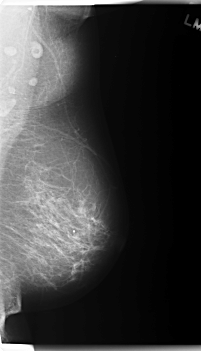

C_0179_1.LEFT_MLO

LEFT_MLO LINES 5960 PIXELS_PER_LINE 3416 BITS_PER_PIXEL 12 RESOLUTION 50 NON_OVERLAY